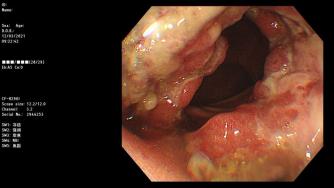

镜下可见

检查所见:进镜可见肛缘上方环周火山样占位病变,质脆易出血。检查结论:直肠癌